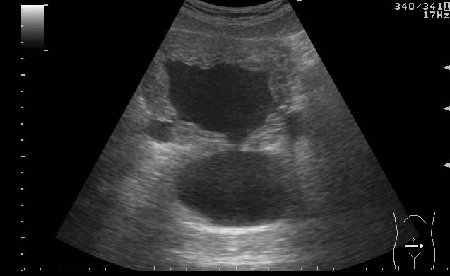

УЗИ мочевого пузыря у пожилого мужчины выявлены следующие изменения.

Signs of chronic urinary retention; evident thickening of the urinary bladder mucosa; large diverticulas. Residual volume evlaluation required; full prostatic assessment is recommended.

But really there are two ones on these pictures.

неравномерное утолщение стенок мочевого пузыря,признаки застоя в мочевом пузыре,расширенные дистальные отделы мочеточников,на первом снимке-дивертикул?слева,уввеличенная отечная простата

Все верно, за исключением того что простаты на картинках нет. Здорово, что Вы заметили расширение мочеточников. Есть также воздух в МП после цистоскопии.